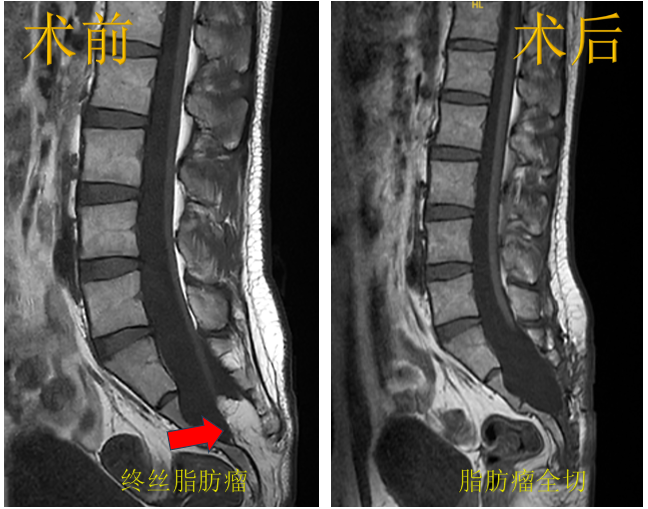

病例2.终丝脂肪瘤,行脂肪瘤切除+终丝切断术。